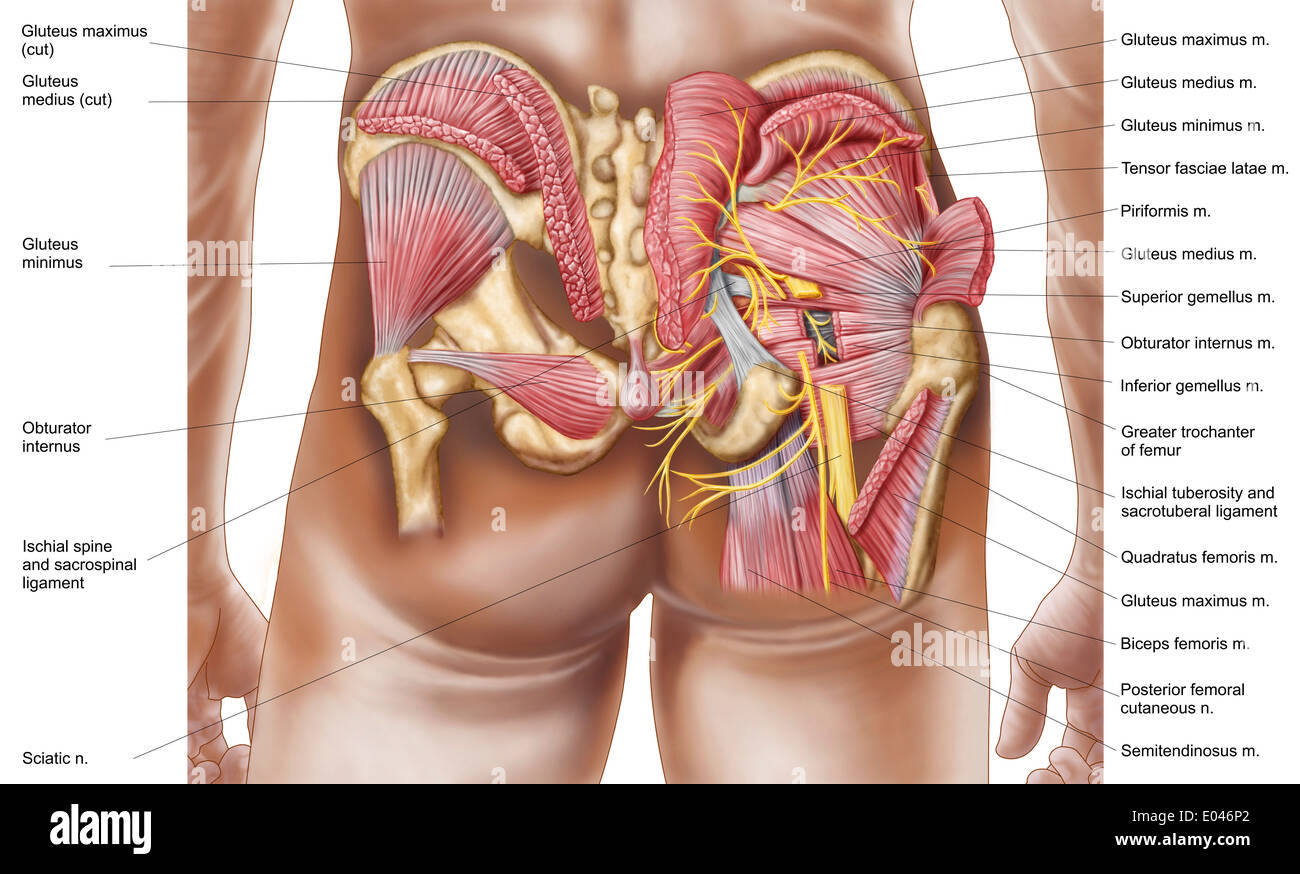

Anatomy of the gluteal muscles in the human buttocks. Stock Photohttps://www.alamy.com/image-license-details/?v=1https://www.alamy.com/anatomy-of-the-gluteal-muscles-in-the-human-buttocks-image68934600.html

Anatomy of the gluteal muscles in the human buttocks. Stock Photohttps://www.alamy.com/image-license-details/?v=1https://www.alamy.com/anatomy-of-the-gluteal-muscles-in-the-human-buttocks-image68934600.htmlRFE046P0–Anatomy of the gluteal muscles in the human buttocks.